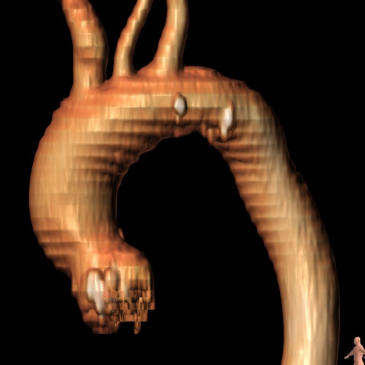

CT分析

主动脉根部尺寸

Annulus

φ24.6mm ,P 77.3mm

LVOT

φ25.9mm,P 81.5mm

SOV Avg φ31.9mm

STJ Avg φ27.0mm

AAO Avg φ32.1mm

钙化

主动脉弓部

投照角度

跨瓣与球扩(短径角度)

瓣膜释放(虚拟Cusp overlap)